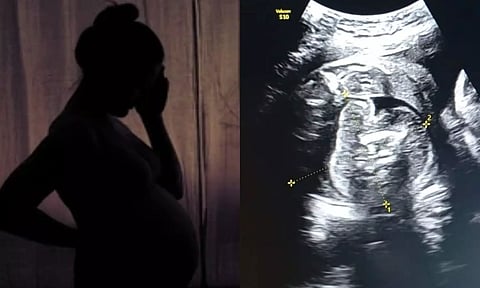

அதாவது பெண்ணின் வயிற்றுக்குள் உண்டாகியுள்ள குழந்தையின் உடலினுள் மற்றொரு முழு வளர்ச்சியடையாத கரு உருவாகி உள்ளது. இதுகுறித்து அந்த மருத்துவமனையின் மகப்பேறு மருத்துவர் பிரசாத் அகர்வால் கூறுகையில், ஆரம்பத்தில் நான் ஆச்சரியமடைந்தேன், பின்னர் கவனமாக ஸ்கேனை மறுபரிசீலனை செய்தேன்.

இது முந்தைய சோனோகிராஃபியில் தவறவிடப்பட்டது. ஏனெனில் இது மிகவும் அரிதான நிலை, இதுபோன்ற ஒரு நிலை இருக்கும் என்று யாரும் கற்பனை கூட செய்ய முடியாது. எனவே, நான் இரண்டு மருத்துவர்களிடம் விரிவான ஆலோசனைக்கு பின் அதை உறுதி செய்தேன் என்று தெரிவித்தார்.

மேலும், குழந்தை பிறந்த பின்னரே இந்த நிலை பெரும்பாலும் கண்டறியப்படும். ஆனால் இப்பெண்ணுக்கு பிரசவத்துக்கு முன்னரே கண்டறியப்பட்டுள்ளது.

இது 5 லட்சத்தில் ஒருவருக்கு மட்டும் நிகழக்கூடிய அரிய வகையான மருத்துவ நிலை. இதுவரை உலகில் வெறும் 200 பேருக்கு மட்டுமே இந்த நிலை உண்டாகியது. அதில் இந்தியாவில் 15-20 பேரில் மட்டுமே இந்த நிலை பதிவாகியது என்று தெரிவித்தார்.

இந்த நிலைக்கான சரியான காரணம் முழுமையாக புரிந்து கொள்ளப்படவில்லை, ஆனால் இது ஒரே மாதிரியான இரட்டையர்களின் வளர்ச்சியின் போது நிகழும் ஒழுங்கின்மையின் விளைவு என நம்பப்படுகிறது.